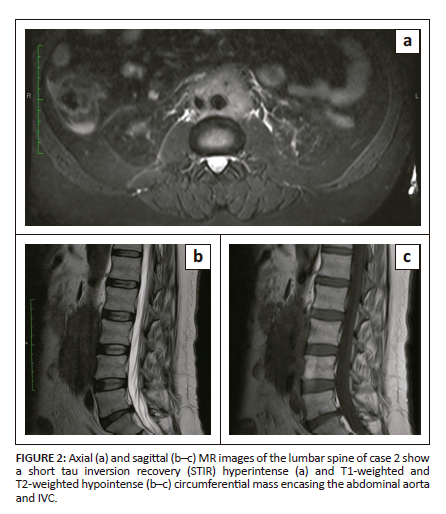

A 53-year-old male presented with chronic low back ache and was referred for MRI of the lumbosacral spine. Imaging revealed a T1-weighted (T1-W) and T2-weighted (T2-W) hypointense mass surrounding the abdominal aorta, hyperintense in signal on short tau inversion recovery (STIR) images (Figure 2a-c). Initially thought to be a nodal mass, contrast-enhanced CT (CECT) was advised. Abdominal CECT revealed a long segment of circumferential, hypodense, mildly enhancing soft tissue mass with an infiltrative and spiculated appearance in the retroperitoneum, completely encasing the infrarenal aorta and inferior vena cava (IVC), extending along the proximal portions of the common iliac arteries without ureteric involvement (Figure 3a and 3b). The patient was extensively evaluated for autoimmune disorders and retroperitoneal fibrosis and serum IgG4 levels were raised at 235 mg/dL. Following the initiation of corticosteroid therapy, the symptoms improved over time and the patient is currently under follow-up.